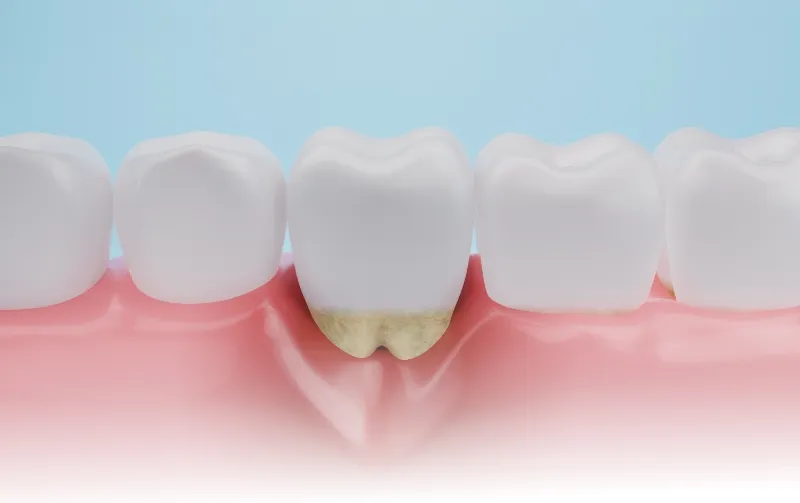

歯肉がさらに赤く腫れるとともに、歯周ポケットが深くなります。歯垢や歯石が溜まるようになり、骨が溶け始めて歯肉が下がってきます。

- STEP 03

中等度歯周炎

歯周ポケットがさらに深くなるとともに、口臭が強くなります。骨が大きく溶けてくるため、歯がグラグラと揺れるようになります。歯根に歯石などが付着している場合は、専用の器具で取り除きます。

- STEP 04

重度歯周炎

歯を支えている骨が半分以上溶けています。ここまでくると歯がグラグラと揺れており、膿も溜まって強い痛みを感じます。そのまま放置すると歯が自然に抜けてしまいます。